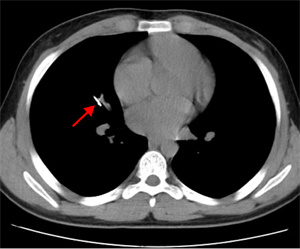

10月18日夜间急诊,来了一位14岁小患者,他在将手表零件放口中玩耍时,不慎吸入气管内。气管内异物是十分危急的,随时可能危及生命。小患者自觉胸闷不适,不时有咳嗽。急诊胸片和CT可以清晰地显示位于右中叶内侧段一长约2.3cm针形异物,两端较尖,急诊科医生程争启紧急联系呼吸与危重症医学科会诊,白克林主任考虑金属异物锐利可能损伤肺内血管造成大出血,准备急诊行内镜取异物。疼痛科、内镜室医务人员迅速反应,立即从家中赶往医院,争分夺秒做好各种术前准备工作。